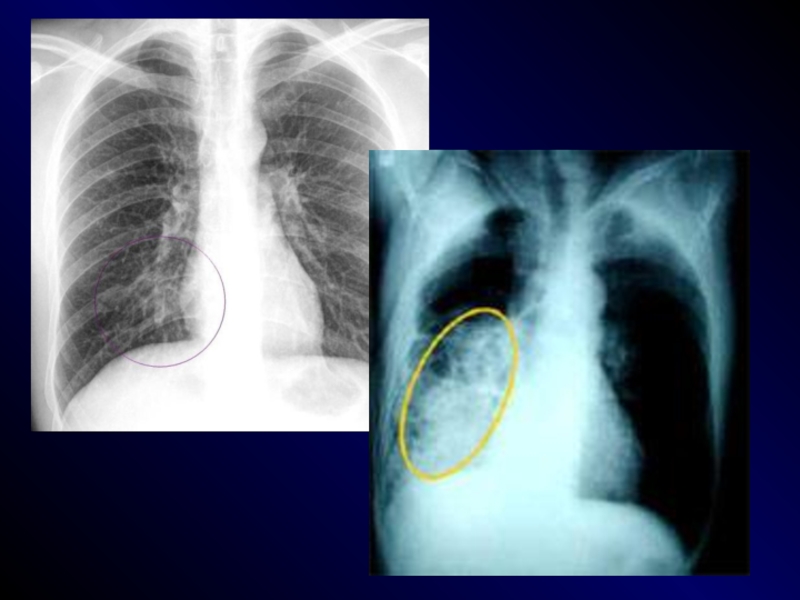

ИНСТРУМЕНТАЛЬНЫЕ МЕТОДЫ ДИАГНОСТИКИ

- РЕНТГЕНОГРАФИЯ ОРГАНОВ ГРУДНОЙ КЛЕТКИ в 2-х проекциях (назначается

и при неполном наборе клинических симптомов)